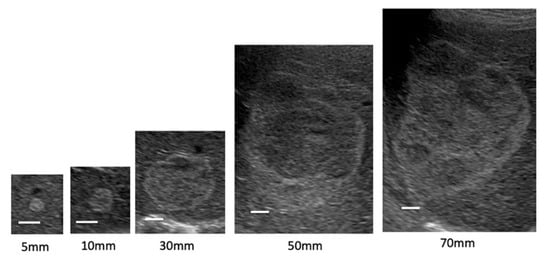

| Echo pattern (n) | |

| Hyperechoic | 209 (74.4%) |

| Hypoechoic | 2 (0.7%) |

| Isoechoic | 1 (0.4%) |

| Mixed | 69 (24.5%) |

| Size of hemangioma (mm) | |

| Small <20 | 190 (67.6%) |

| Medium 20–40 | 67 (23.9%) |

| Large >40 | 24 (8.5%) |

| Echo pattern | <0.0001 | |||

| Homogenous type (n) | 189 (99.5%) | 23 (34.3%) | 0 (0%) | |

| Mixed type (n) | 1 (0.5%) | 44 (65.7%) | 24 (100%) | |